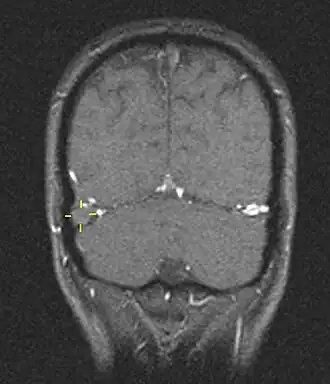

La trombosis del seno venoso cerebral (CVST) es la presencia de trombosis (coágulo sanguíneo) en el seno venoso dural, que recibe sangre de venas externas e internas del cerebro. Los síntomas de esta enfermedad pueden incluir dolor de cabeza, visión anormal, cualquiera de los síntomas de un accidente cerebrovascular (debilitamiento de los músculos de la cara y extremidades de una mitad del cuerpo) e infartos. El diagnóstico se realiza normalmente por tomografía axial computarizada (CT/CAT scan) o resonancia magnética (MRI) empleando el contraste radiológico para demostrar obstrucción de los senos venosos por trombos.[1]

Hay varias formas de neuroescaneo que pueden determinar la presencia de la trombosis del seno venoso cerebral. Los edemas cerebrales e infartos venosos pueden hacerse visibles en cualquier modalidad, pero para la detección del trombo sí, el tipo de escaneo más usado comúnmente son la tomografía axial computarizada (CT) y la resonancia magnética (MRI). Ambas usan varios medios de radiocontraste para elaborar un venograma y visualizar las venas en torno al cerebro.[1]

La tomografía axial computarizada tiene una capacidad de detección que para algunos expertos supera la de la resonancia magnética. Esta prueba se basa en la inserción, a través de una inyección en la vena (normalmente en el brazo), de una sustancia radiopaca. Tras un tiempo, el que tarda el torrente sanguíneo en llevar la sustancia al cerebro, el escaneo se realiza. La sensibilidad de este test es de 75-100% (detecta de 75 a 100% de todos los coágulos presentes), y una especificidad de 81-100% (sería incorrectamente positivo en un 0-19%).[6]

La resonancia magnética venosa emplea los mismos principios, pero la modalidad de escaneo usada es la resonancia magnética. La MRI tiene la ventaja de ser mejor a la hora de detectar peligro para el cerebro como resultado del incremento de la presión en las venas obstruidas. No obstante, este mecanismo no se encuentra disponible en muchos hospitales y su interpretación puede resultar dificultosa.[6]